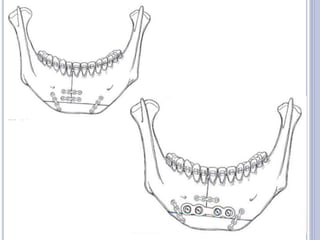

7. INTRAORAL MODIFIED SAGITTAL SPLIT

OSTEOTOMY

 Also called as - Bilateral Sagittal Split Osteotomy

 It is performed on the mandibular ramus and body.

 First described by Obwegesser and Trauner and later

modified by Dal Pont, Hunsuck and Epker.

 Transoral incision, similar to that used for IVRO.

 The osteotomy splits the ramus & the posterior body of the

mandible sagittally, which allows either setback or

advancement.

 This is a highly cosmetic procedure, as it is done intraorally,

plus, there is broader bony contact of the osteotomised

segments, ensuring good healing.

Drawback:

* High level of operative skill is required.

* Experience to minimize the surgical complication.